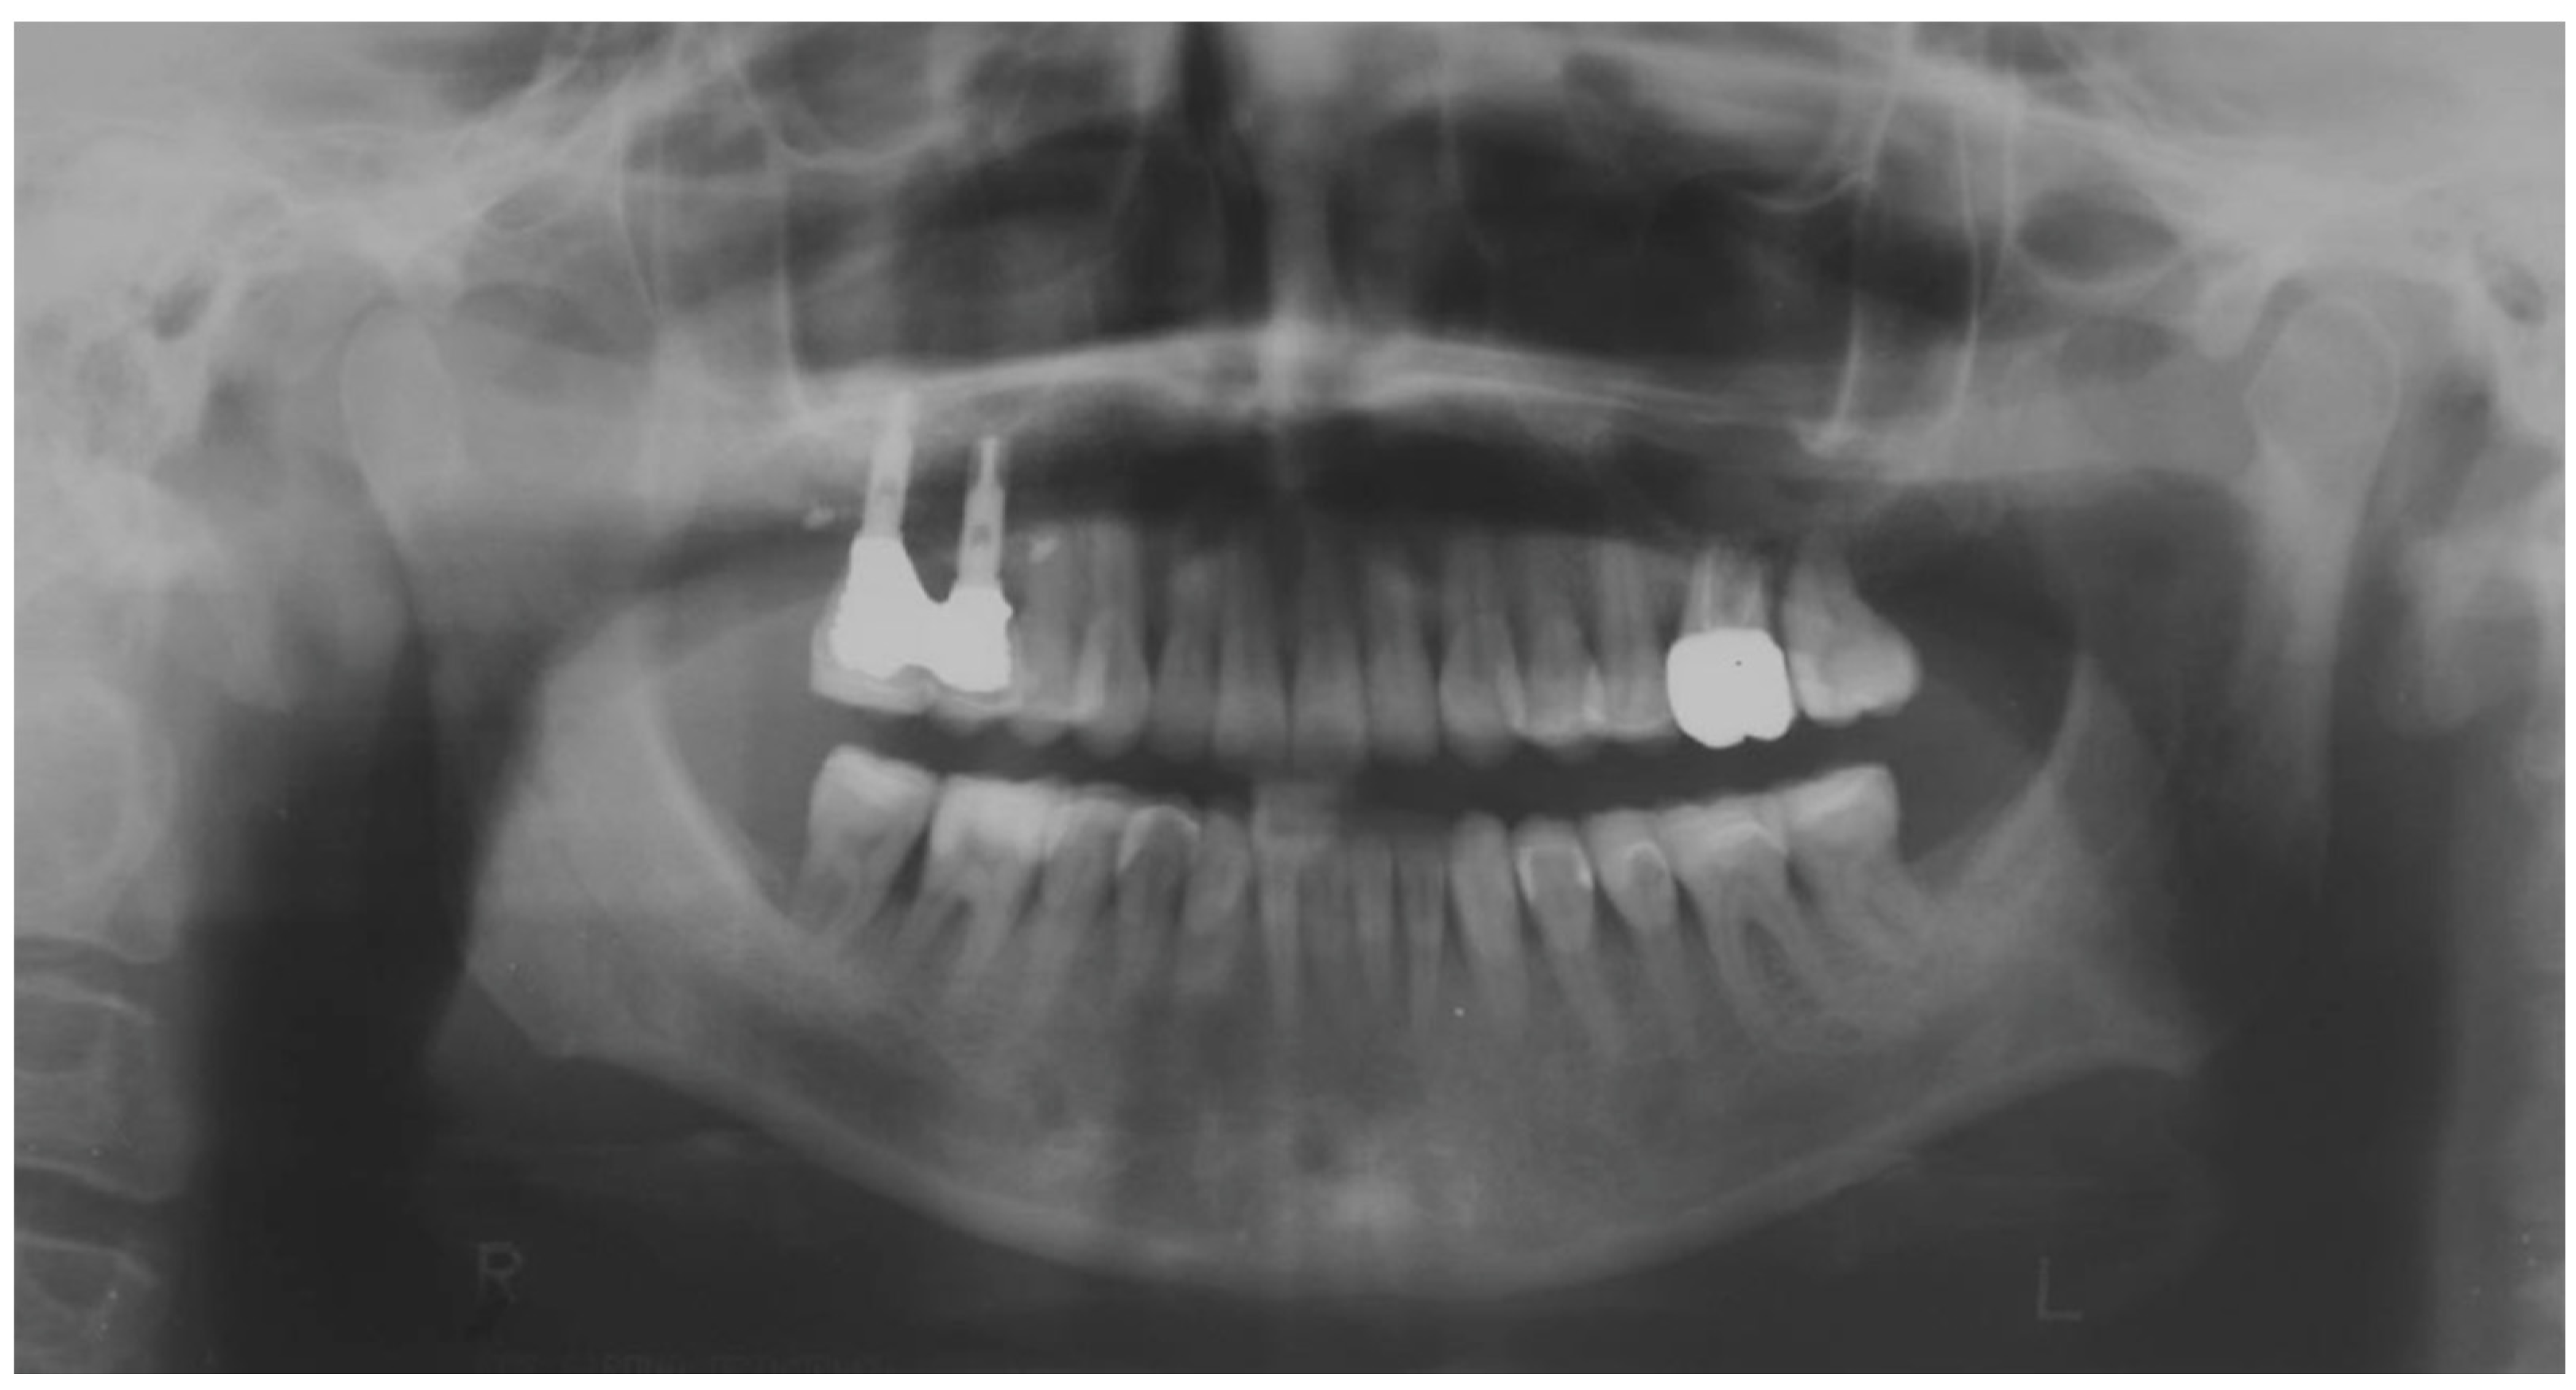

| Before | After | |

|---|---|---|

| Disharmonious smile | Yes | No |

| Dyschromia, dysmorphia, abrasions, and erosions of teeth | Yes | No |

| Anterior crowding in the upper arch | Yes | No |

| Anterior crowding in the lower arch | Yes | No |

| Upper transverse discrepancy | Yes | No |

| Presence of buccal corridors or black tunnels | Yes | No |

| Curve of Spee alteration | Yes | No |

| Curve of Wilson alteration | Yes | No |

| Functional movements with altered guides | Yes | No |

| Pain and/or noise ATM | Yes | No |